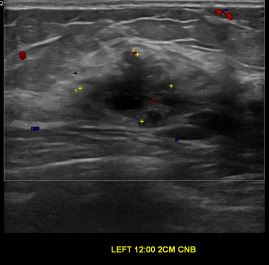

상기환자는 외부검사 이상소견으로 내원하신 60대초반 여성분으로 의심스러운 좌측혹

조직검사 시행해 유방암으로 진단되었습니다